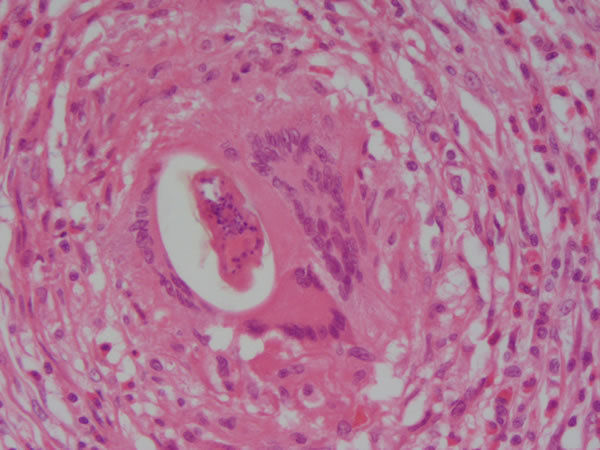

Intestino grosso - epit. cilindrico simples Infl. cronica granulomatosa Ovo calcificado de S. mansoni no centro de um granuloma Causas: Infecções persistentes, reação de hipersensibilidade, exp. agentes tóxicos |

Intestino grosso -epit. cilindrico simples/ mucosa e submucosa Infl. crônica granulomatosa Macrófago multinucleado englobando ovo de S. mansoni |